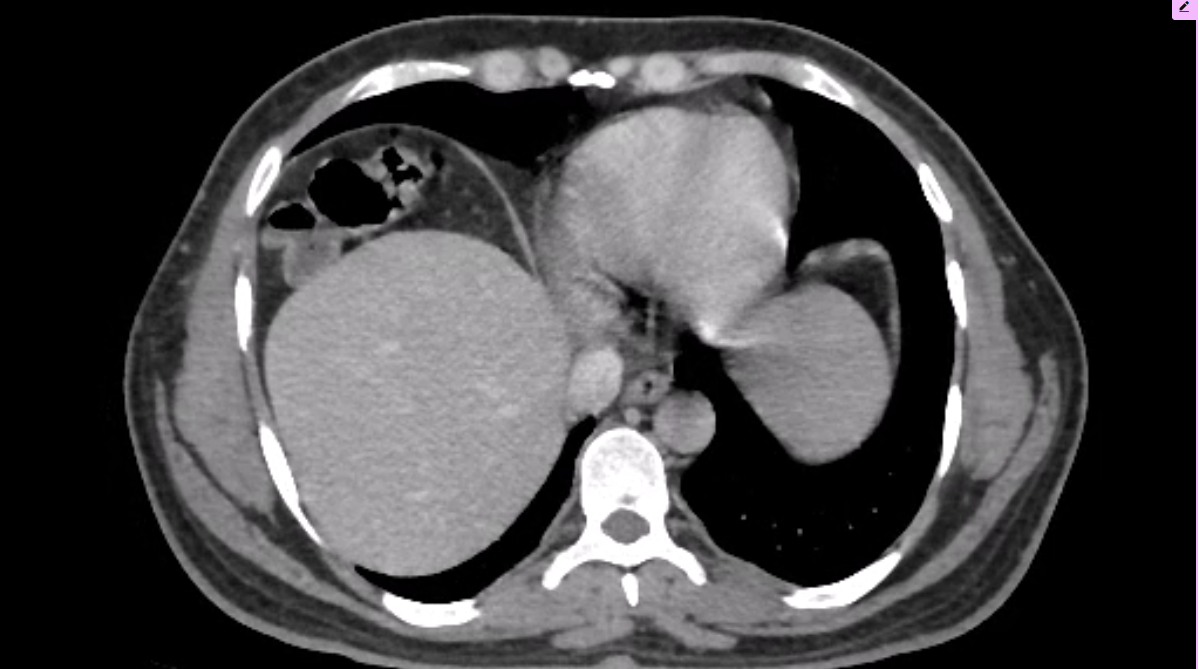

Body imaging is central to modern medicine—from early diagnosis to guiding treatment and follow-up. As our field continues to evolve, our mission is to embrace innovation responsibly, apply it ethically, and translate it into meaningful clinical impact.